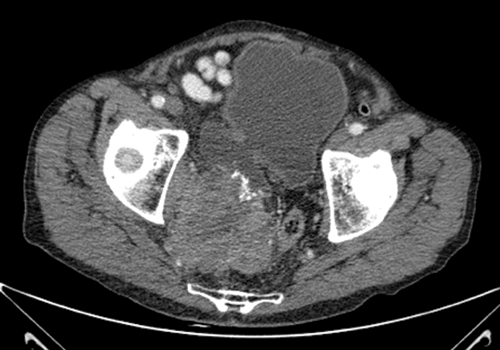

Case 2

1. What is the diagnosis?

2. What local effects can this mass cause?

Large tumour within bladder diverticulum.

-

Invasion and compression of local structures causing: haematuria, pain due to mass effect, neuropraxia (sacral nerve compression), altered bowel habit (rectal compression).